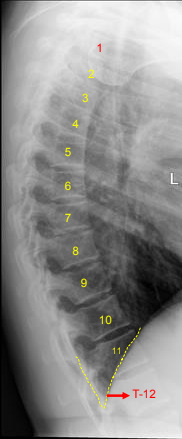

Lateral T-Spine: Eval Criteria

Thoracic vertebral bodies, intervertebral joint spaces, and intervertebral foramina

T1 to T3 will not be well demoed

Intervertebral disk spaces should be seen

Excessive rotation indicated by > 1/2” of space between separated posterior ribs

Lateral T-Spine: Is this Image Good?

No

Missing part of T1

Blurry - we want ribs blurred not the vertebrae

Ask pt to stay still while taking breaths

Separated posterior ribs indicate rotation at the superior aspect of spine

Overexposed

Decrease mAs